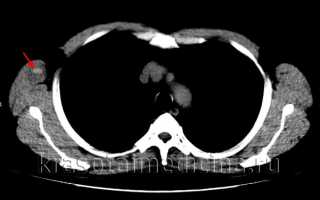

image

КТ ОГК. Гиперденсное скопление крови в толще мышечного массива грудной стенки справа, окруженное зоной отека.